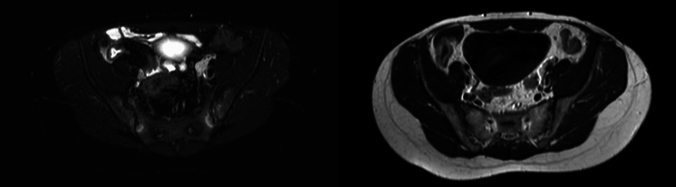

Magnetic resonance enterography (MRE) is recommended for the assessment of small intestine alterations in Crohn's disease (CD). Sacroiliac joints (SIJs) imaging has a central role in the early diagnosis of sacroiliitis (SI). MRE can evaluate both acute and structural findings of SIJs. We aimed to assess the prevalence of SI detected by MRE in a cohort of CD patients, and the associations of SI with demographic and clinical features and with intestinal MRE findings. Two hundred patients affected by CD (M:F 1:1, median age 49.5 (22.5) years, median CD duration 4.75 (16.2) years) tested with MRE between 2011 and 2023 were selected. They discontinued tumor necrosis factor α inhibitors (TNFαi) at least 3 months before the MRE execution. Most patients had an ileal CD location (65.0%) and a stricturing behavior of disease (50.0%). Thirty-five percent of patients underwent ileocecal resection. One out of ten patients were treated with at least one TNFαi. Active SI, capsulitis, erosions, sclerosis, and ankylosis were present in 10.5%, 0.5%, 2.0%, 2.5%, and 1.5%, respectively. No significant correlations have been evidenced between the presence of SI and demographic and clinical variables. The presence of an asymmetric hyperenhancement of the bowel wall was instead directly associated with the presence of SI (OR 8.61, 95% CI 1.47-50.4, p = 0.017). In this study, subclinical SI is a frequent finding in CD patients being present in one out of ten MRE examination. This phenomenon was significantly associated with asymmetric mural enhancement, a specific CD intestinal lesion at MRE.

Abstract Image